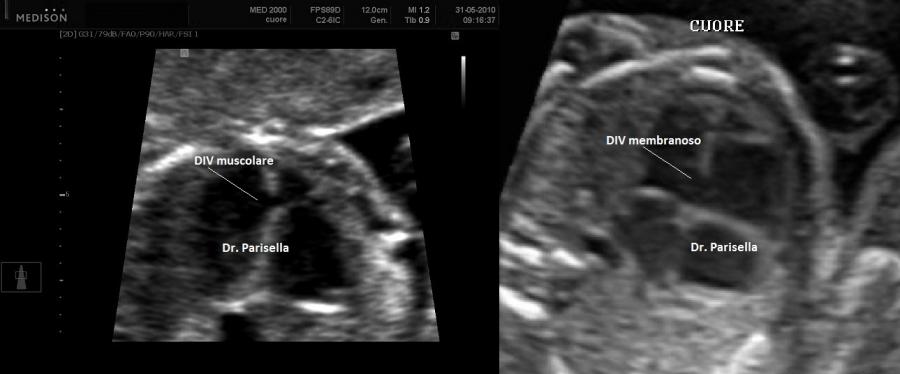

incostante è la presenza di anomalie della colonna vertebrale, cardiopatie congenite.

• cardiopatie congenite